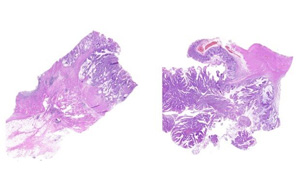

研究揭示了同時(shí)發(fā)生APC和MLH1種系突變的結(jié)直腸腫瘤的體細(xì)胞突變譜

近日,中國(guó)科學(xué)院合肥物理科學(xué)研究院與安徽醫(yī)科大學(xué)第二醫(yī)院的合作課題組首次解剖了家族性結(jié)直腸癌APC和MLH1基因突變共遺傳的體細(xì)胞突變譜。